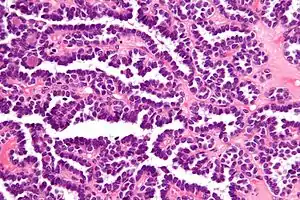

| Micrograph of a metanephric adenoma with structures reminiscent of those seen in papillary renal cell carcinoma. H&E stain. | |

Metanephric adenoma (MA) is a rare, benign tumour of the kidney, that can have a microscopic appearance similar to a nephroblastoma (Wilms tumours),[1] or a papillary renal cell carcinoma.

Metanephric adenoma is diagnosed histologically. The tumours can be located at upper pole, lower pole and mid-hilar region of the kidney; they are well circumscribed but unencapsulated, tan pink, with possible cystic and hemorrhagic foci. They show a uniform architecture of closely packed acinar or tubular structures of mature and bland appearance with scanty interposed stroma.[3][4][5][6][7] Cells are small with dark staining nuclei and inconspicuous nucleoli. Blastema is absent whereas calcospherites may be present. Glomeruloid figures are a striking finding, reminiscent of early fetal metenephric tissue. The lumen of the acini may contain otherwise epithelial infoldings or fibrillary material but it is quite often empty. Mitoses are conspicuously absent.[3][4][5][6][7] In the series reported by Jones et al. tumour cells were reactive for Leu7 in 3 cases of 5, to vimentine in 4 of 6, to cytocheratin in 2 of 6, to epithelial membrane antigen in 1 of 6 cases and muscle specific antigen in 1 of 6.[5] Olgac et al. found that intense and diffuse immunoreactivity for alpha-methylacyl-CoA racemase (AMACR) is useful in differentiating renal cell carcinoma from MA but a panel including AMACR, CK7 and CD57 is better in this differential diagnosis.[8] Differential diagnosis may be quite difficult indeed as exemplified by the three malignancies initially diagnosed as MA that later metastasized, in the report by Pins et al.[9]